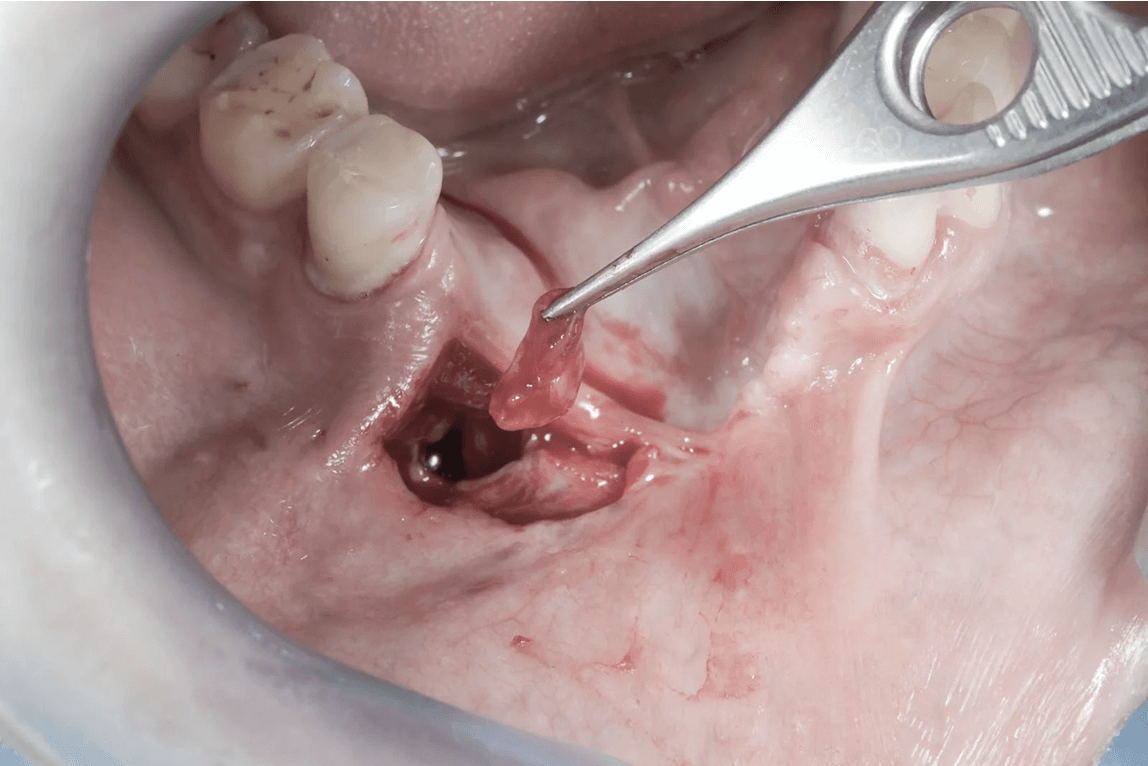

Chirurgicznym usunięciem zęba nazywamy zabieg ekstrakcji zęba lub jego fragmentu przy użyciu bardziej złożonych technik operacyjnych i zaawansowanego instrumentarium. Tych sposobów używamy w sytuacji, gdy mamy do czynienia z bardzo zniszczoną strukturą zęba, trudnym położeniem zęba czy też jego złamaniem w taki sposób, że pozostały fragment uniemożliwia prostą ekstrakcję.

Przy łatwym dostępie do zębów ósmych usunięcie zazwyczaj kończy się ekstrakcją prostą.W sytuacji zęba zatrzymanego lekarz decyduje o jego chirurgicznym usunięciu. Po wyjęciu zęba oczyszcza zębodół i zabezpiecza szwami ranę.Przy prostej i chirurgicznej ekstrakcji pacjent jest znieczulony miejscowo i nie odczuwa bólu. W sytuacji kwalifikacji pacjenta do ekstrakcji wszystkich zatrzymanych zębów mądrości podczas jednego zabiegu, ze względu na jego złożoność i czas wykonania procedury można wykonać zabieg w znieczuleniu ogólnym.